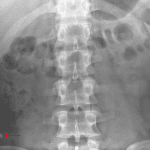

Age: 19

Sex: Male

Indication: Abdominal pain

Findings

- 7 mm calcific density overlies the right lower quadrant

- Nonobstructive bowel gas pattern

Diagnosis

- Appendicolith

Sample Report

Sample Report

7 mm calcific density overlies the right lower quadrant, which though nonspecific could represent an appendicolith. Consider CT for further evaluation.

Nonobstructive bowel gas pattern.